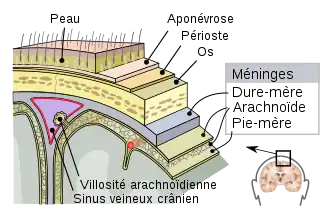

Les méninges sont des membranes superposées qui, avec le liquide cérébrospinal, enveloppent et protègent le névraxe (encéphale et moelle spinale), au sein de la boite crânienne et du canal vertébral. On distingue trois couches de tissu : la pie-mère, l'arachnoïde et la dure-mère. La pie-mère est une membrane fragile et imperméable, adhérente à la surface de l'ensemble du névraxe. L'arachnoïde est une sorte de sac qui contient le névraxe et la pie-mère, baignés dans le liquide cérébrospinal. La dure-mère est une membrane plus solide et accolée à l'arachnoïde. La dure-mère est également accolée à la paroi de la boite crânienne, mais elle est séparée de la paroi du canal vertébral par un espace graisseux.